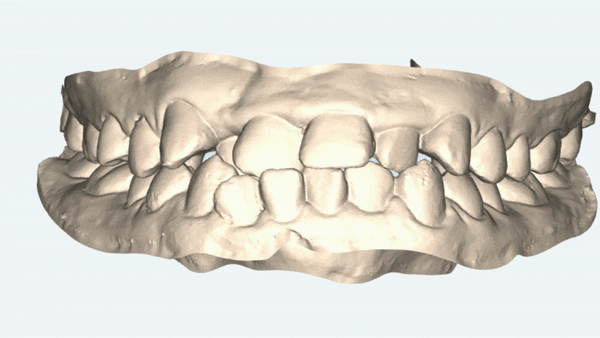

치아가 모두 고르게 펴질수 있는 공간이 협소해서

발치교정도 생각해 볼수 있었으나,

환자의 안모 등 여러가지 사안들을 고려해서

비발치 교정에 적합한 '데이몬교정장치' 로 잠실치아교정을 진행했습니다.

앞니 충치치료와 , 어금니 충치치료 후 교정치료가 완료된 사진입니다

악궁 확장 기능에 탁월한 데이몬 클리어 교정장치를 통해

발치를 하지 않고 비발치교정으로 약 1년 8개월의 기간동안 진행 해드렸습니다 ^^